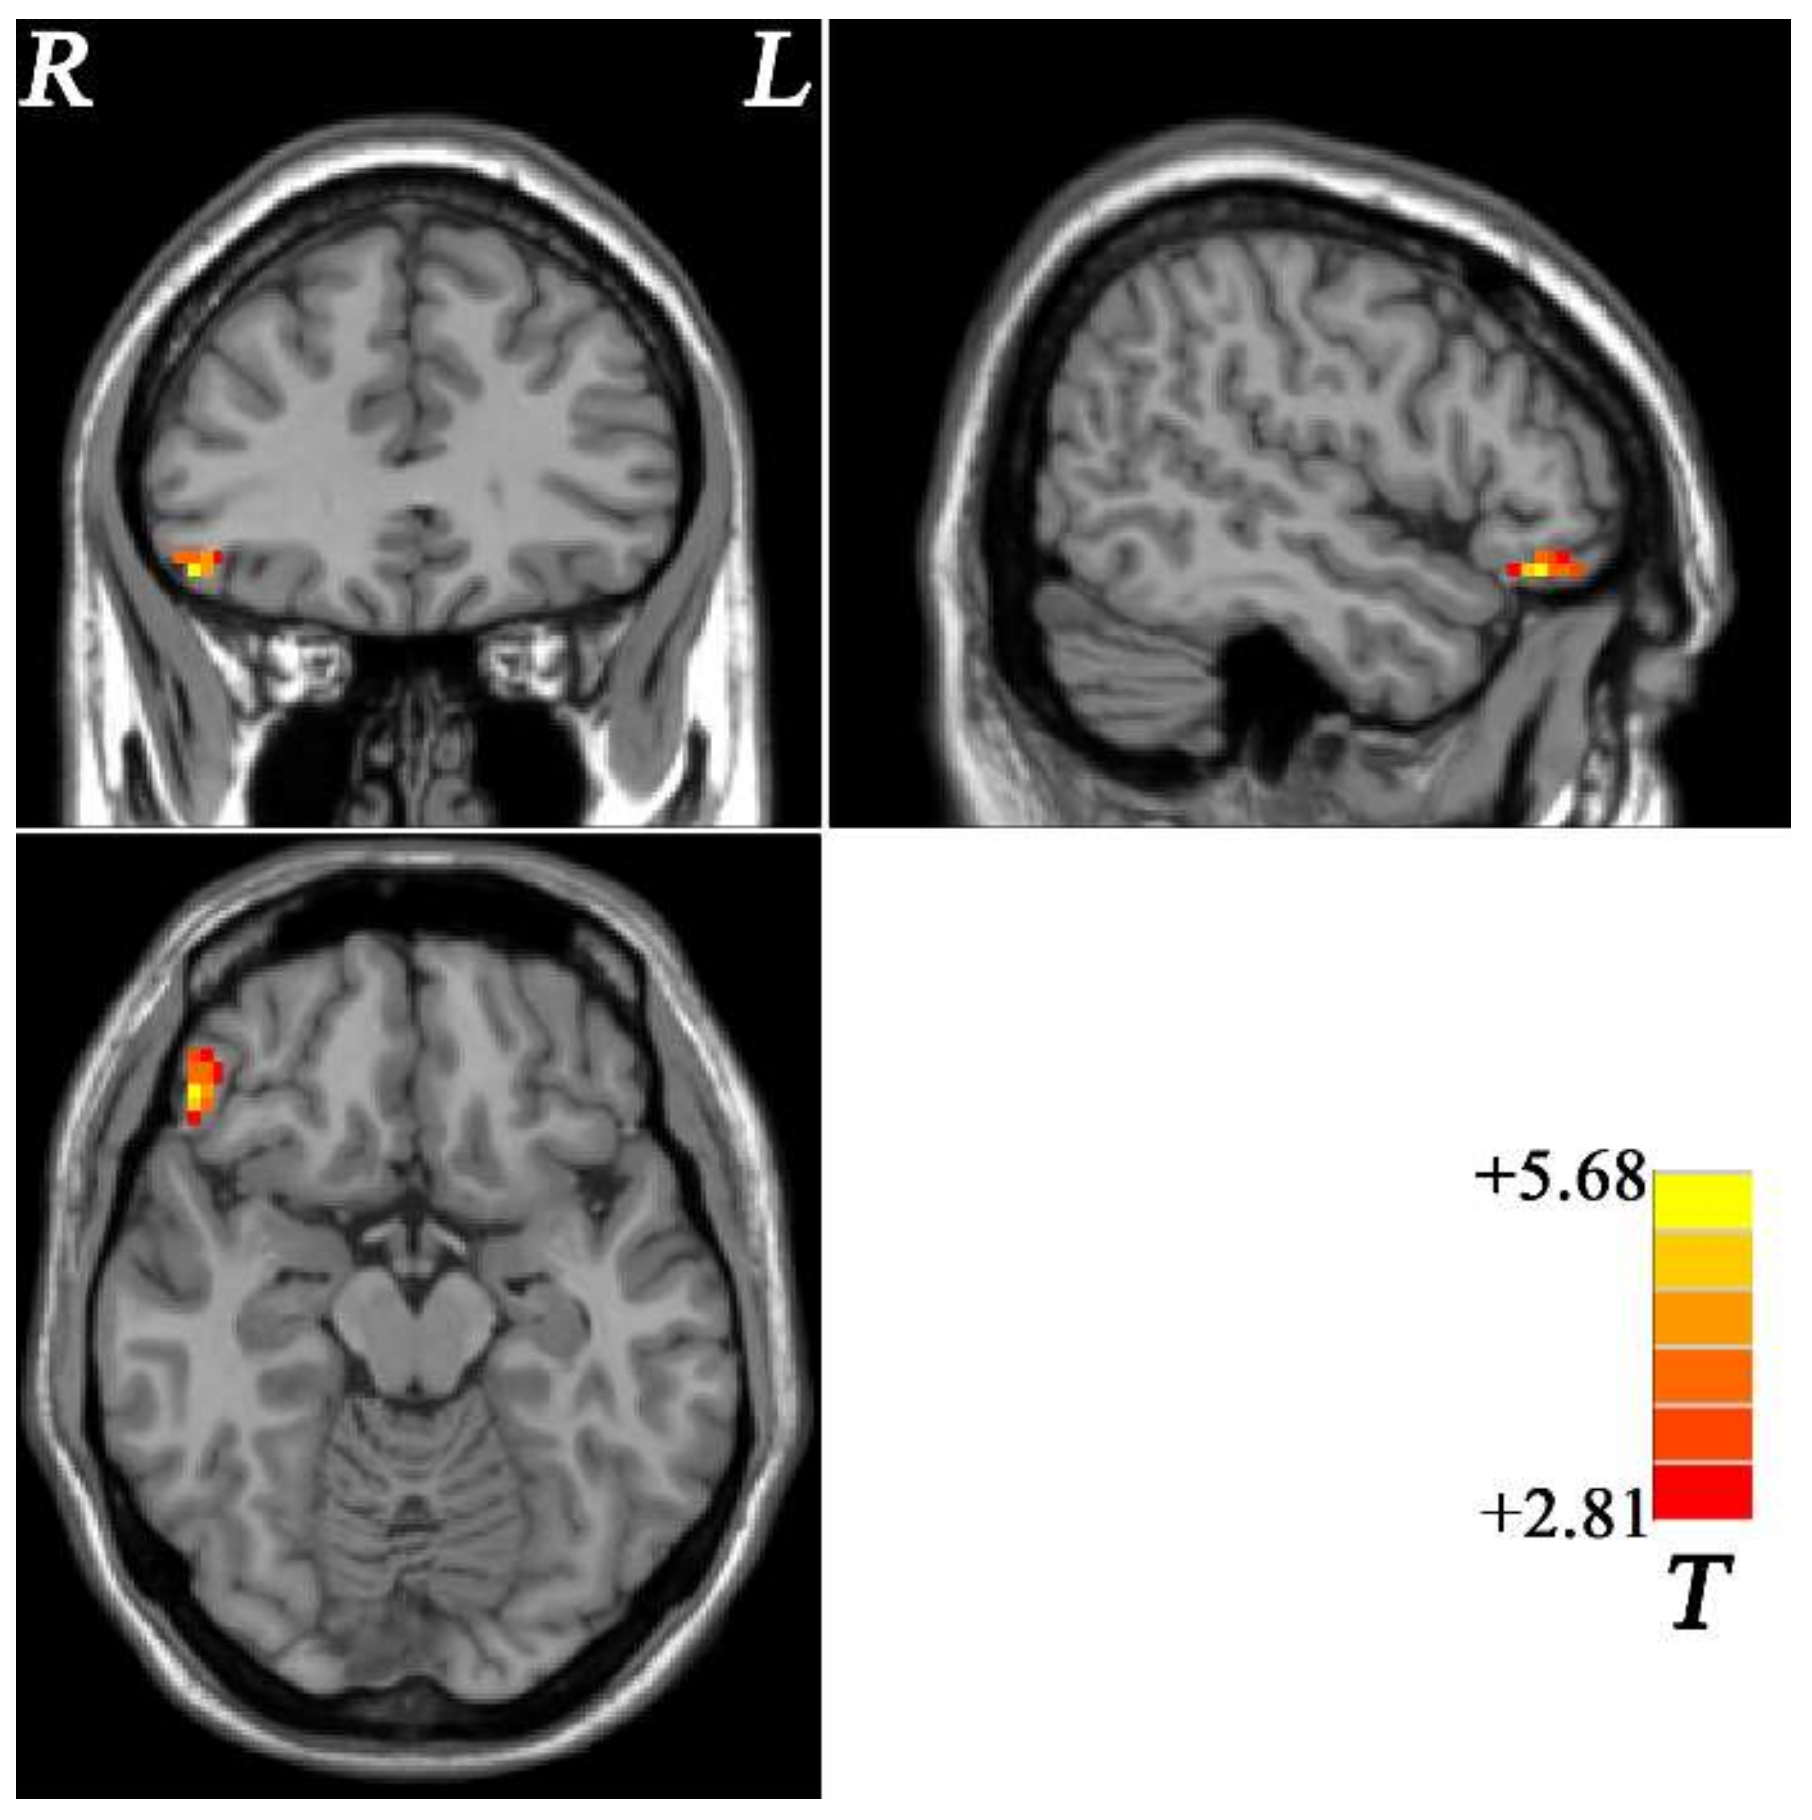

3.2. Group Differences of fALFF within the Fronto-Limbic Network

| Cluster Location | Peak (MNI) | Number of Voxels | T Value | ||

|---|---|---|---|---|---|

| x | y | z | |||

| fALFF | |||||

| Right OFC | 51 | 33 | −15 | 30 | 5.6825 |